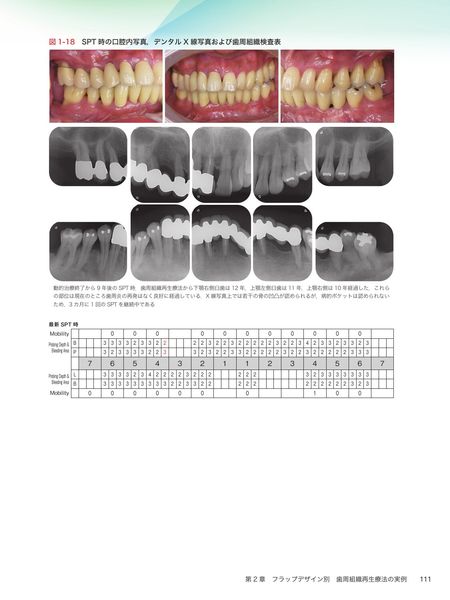

第2章 フラップデザイン別 歯周組織再生療法の実例